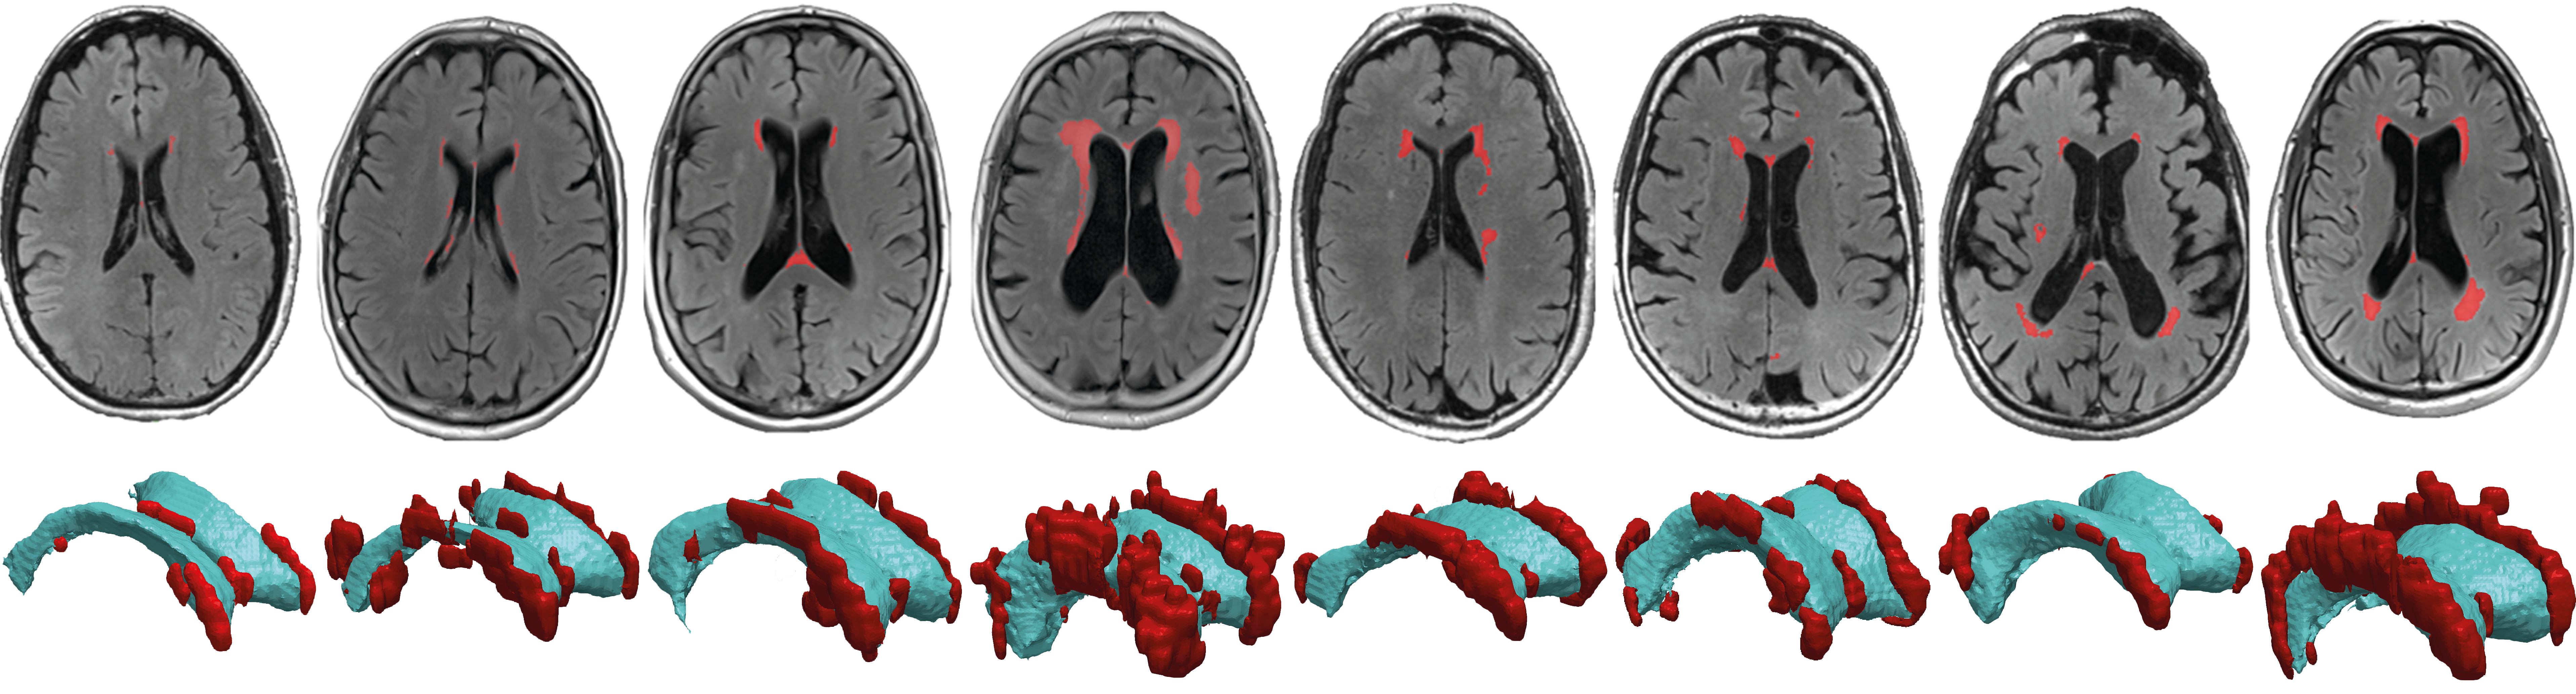

These lesions — known as deep and periventricular white matter hyperintensities because they show up as bright white patches on MRI scans — are poorly understood. But they are not uncommon: most people have some by the time they reach their 60s, and changes only increase with age. The more lesions that accumulate and the faster they grow, the more prone we become to cognitive impairments ranging from memory problems to motor disorders.

Using MRI scans from eight healthy subjects, Weickenmeier worked with Valery Visser, now a doctorate student at the University of Zurich, and Henry Rusinek, a radiologist at NYU Grossman School of Medicine, to develop an individualized computer model of each subject’s brain. The team mapped the strain placed on ventricular walls, the linings of fluid-filled chambers deep in the brain, as waves of pressure pulse through the subject’s cerebral spinal fluid, or CSF. They found that hyperintensities tend to occur near areas that must stretch more to accommodate pressure changes of the circulating CSF because, as such areas wear thin, CSF can leak into the brain and cause lesions.

“The cell wall that lines the ventricles wears out over time, like a balloon that’s repeatedly blown up and deflated,” said Weickenmeier. “And the stresses aren’t uniform — they’re defined by the geometry of the ventricle, so we can predict where these failures will occur.”

The team’s research, published recently in Scientific Reports, used 2D imaging showing a cross-section of the brain, but Weickenmeier’s team has since expanded its research to a full 3D model of the brain. Next, Weickenmeier hopes to use advanced MRI technologies developed at Stevens to study the movement of the ventricle wall directly.